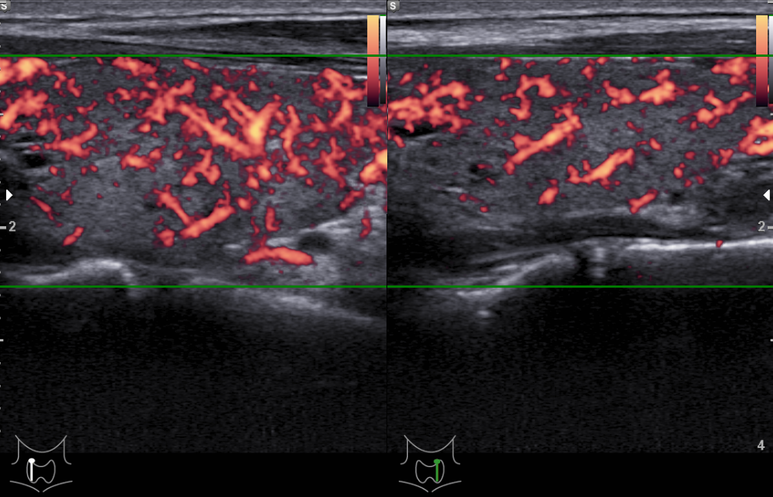

도플러 패턴도 강해짐

hilum의 혈관이 잘 관찰됨